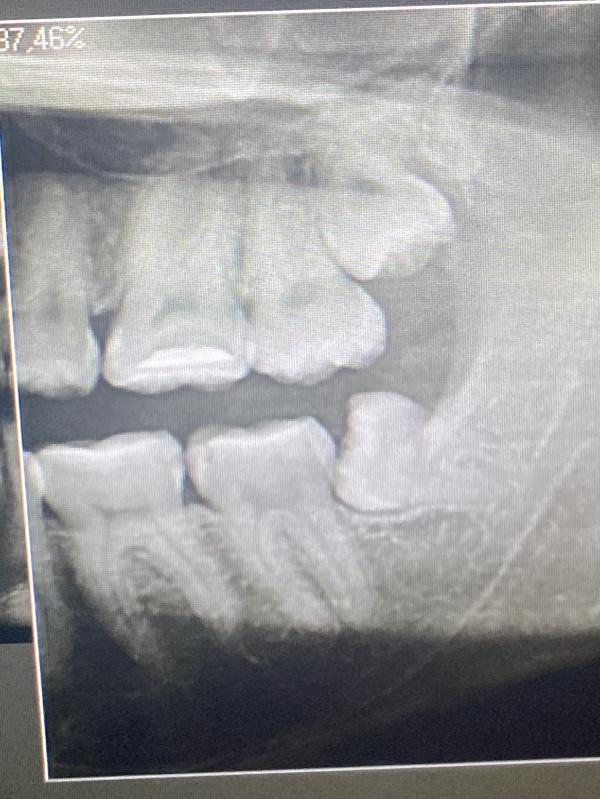

Вы уже удалили нижнюю 8ку? Я точно такую же вчера удалила, бесплатно 👍 год боялась и тянула, но решилась и Слава Богу! 5 минут и всё готово!